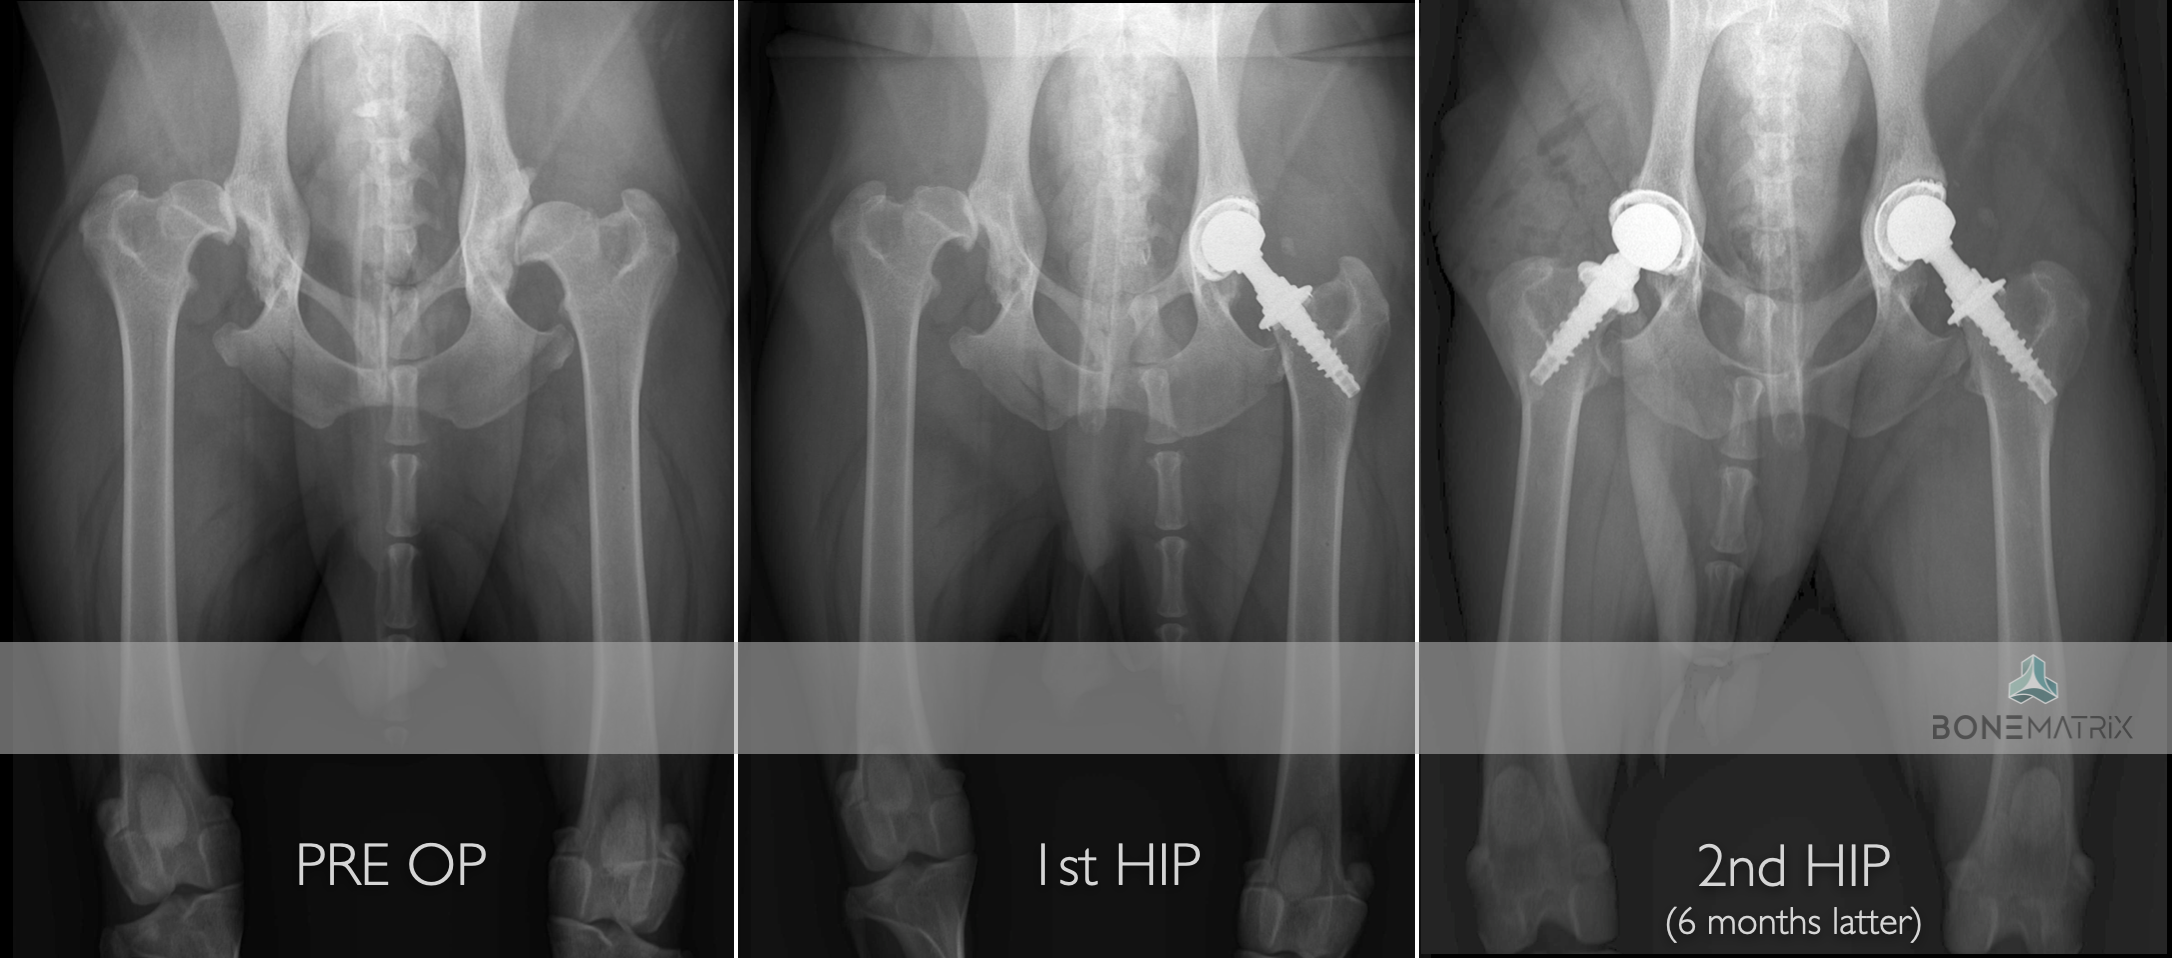

A Prótese Total de Anca (THR - total hip replacement) é um procedimento cirúrgico onde a articulação coxofemoral é completamente substituída por uma nova articulação protésica.

Em medicina humana, esta é a cirurgia de eleição utilizada como tratamento de quadros de osteoartrite severa, apresentando taxas de sucesso extremamente elevadas. Da mesma forma, esta é a solução mais avançada no paciente canino para o tratamento de osteoporose-artrite e displasia de anca, sendo a única capaz de restaurar uma função normal, com normal amplitude e ausência de dor.

A cirurgia consiste na eliminação das duas componentes articulares (cabeça femoral e acetábulo) com alterações patológicas e substituição por uma articulação protésica constituída também por duas peças que mimetizam a função da articulação anterior.

Qual a taxa de sucesso esperada?

Esta técnica de uma taxa de sucesso de 95%, sendo a taxa de complicações maiores cerca de 10%.

DPO (double pelvic osteotomy) é um procedimento preventivo realizado em pacientes onde o despiste de displasia de anca prevê o desenvolvimento desta doença.

Inicialmente deve ser realizado um despiste de displasia de anca com recurso a um estudo radiográfico especifico para que o paciente seja avaliado e seja definido como um bom candidato à aplicação desta técnica.

O que é?

A DPO consiste na realização de dois cortes ao nível da pélvis que permitem a rotação do fragmento criado. Este fragmento inclui a porção articular da pélvis, na articulação coxofemoral (o acetábulo).

Ao rodar este fragmento conseguimos uma maior cobertura da cabeça femoral pelo acetábulo, impedindo o movimento de saída da cabeça femoral de dentro do acetábulo. Ao impedir este movimento (laxitude articular) impedimos o desenvolvimento de lesões de osteoartrite provocada por ele, e desta forma impedimos o desenvolvimento da doença de displasia de anca.

Após rotação do fragmento, este é estabilizado na posição pretendida com recurso a placas bloqueadas especializadas para a realização desta cirurgia, garantindo assim a cicatrização do osso no ângulo previamente definido.

Este procedimento pode ser realizado bilateralmente no mesmo momento cirúrgico.

Quem são os bons candidatos para realização de DPO?

Este procedimento deve ser realizado idealmente aos 5.5 meses daí aí importância dos despiste de displasia de anca serem realizados muito cedo na vida do animal.

Os pontos essenciais que definem um bom candidato são a idade do paciente, desenvolvimento mínimo de osteoartrite a nível articular e presença de um sinal de Ortolani positivo (teste realizado durante a consulta pré-despiste).

Após a realização desta cirurgia a claudicação irá resolver-se por norma em 3 meses após a cirurgia.

A taxa de sucesso de aplicação desta técnica é de cerca de 90% onde os paciente apresentam desde uma melhoria significativa até ao retorno à condição normal. Em alguns casos podem ser desenvolvidas alterações de osteoartrite ligeiras, mas por norma não são suficientes para provocar claudicação até que o paciente seja geriátrico.

Este procedimento preventivo é preferido a outras técnicas similares como a TPO por resultar num pós cirúrgico menos doloroso por comparação.

Que complicações podem surgir?